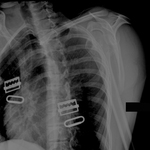

Luxação do cotovelo direito: cabeça do rádio deslocada (a), olécrano (b) e tendão do tríceps tenso (c), resultando em uma depressão na pele (d) logo proximal à cabeça do rádio

Lui TH, et al. BMJ. 2020 Oct 8:371:m3494; usado com permissão